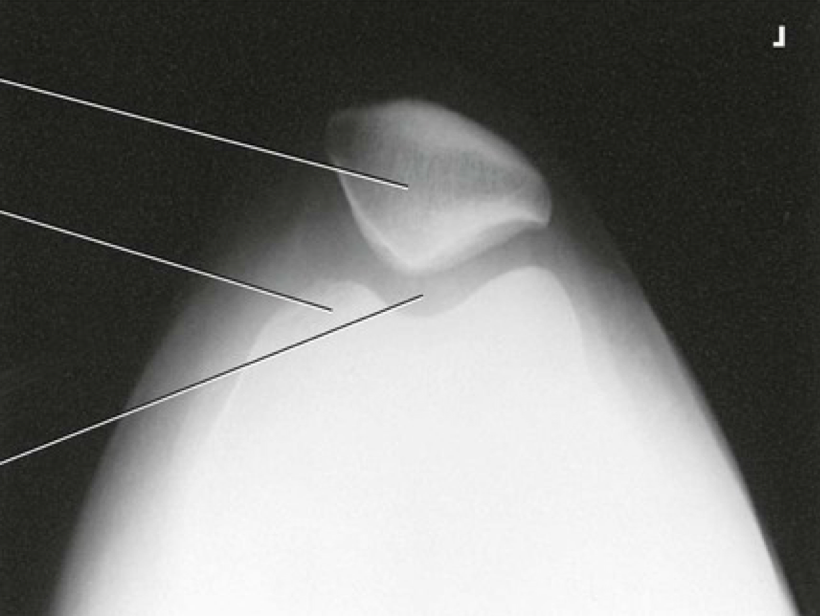

Question 9

Question

Label the image

Image:

0a2a07d9-1669-44af-a36a-b73fb8913c1f (image/png)

Answer

femur

lateral condyle

tibia